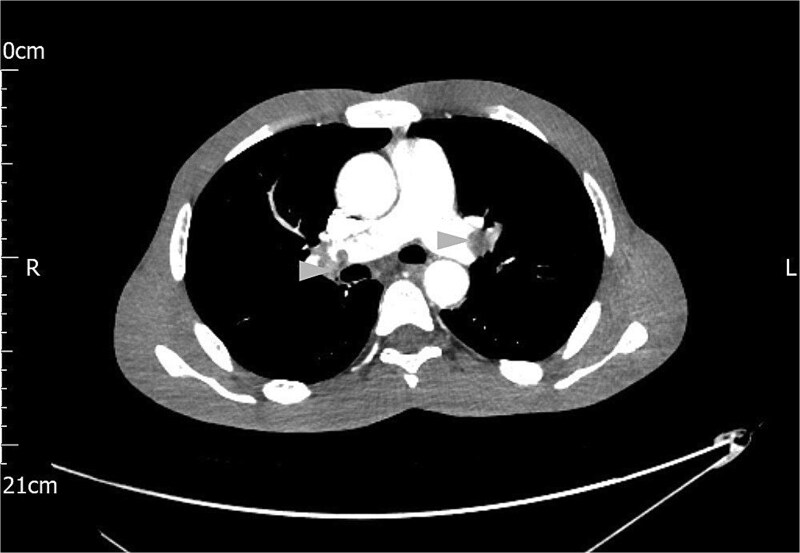

Acute necrotising pancreatitis can lead to severe vascular complications, including venous thrombosis, pseudoaneurysm, and haemorrhage. Acute haemorrhagic pancreatitis, though rare, is life-threatening. Contrast-enhanced computed tomography (CT) scan is the preferred diagnostic tool, with image-guided embolisation as the primary treatment for bleeding vessels. Surgery may be necessary when radiological methods fail. A 39-year-old male with recurrent abdominal pain, distension, and weight loss was initially misdiagnosed with intra-abdominal malignancy based on CT findings of omental deposits. Elevated amylase levels and haemorrhagic ascetic fluid prompted further investigations. A rapid haemoglobin drop and clinical deterioration led to diagnostic laparoscopy, confirming acute haemorrhagic pancreatitis. This case highlights the diagnostic challenges of this condition, which may present subtly and evade standard imaging, resulting in delayed treatment. Clinicians should suspect haemorrhagic pancreatitis in patients with acute abdominal pain, elevated amylase or lipase, and ascites. Early recognition and intervention are crucial for better outcomes.